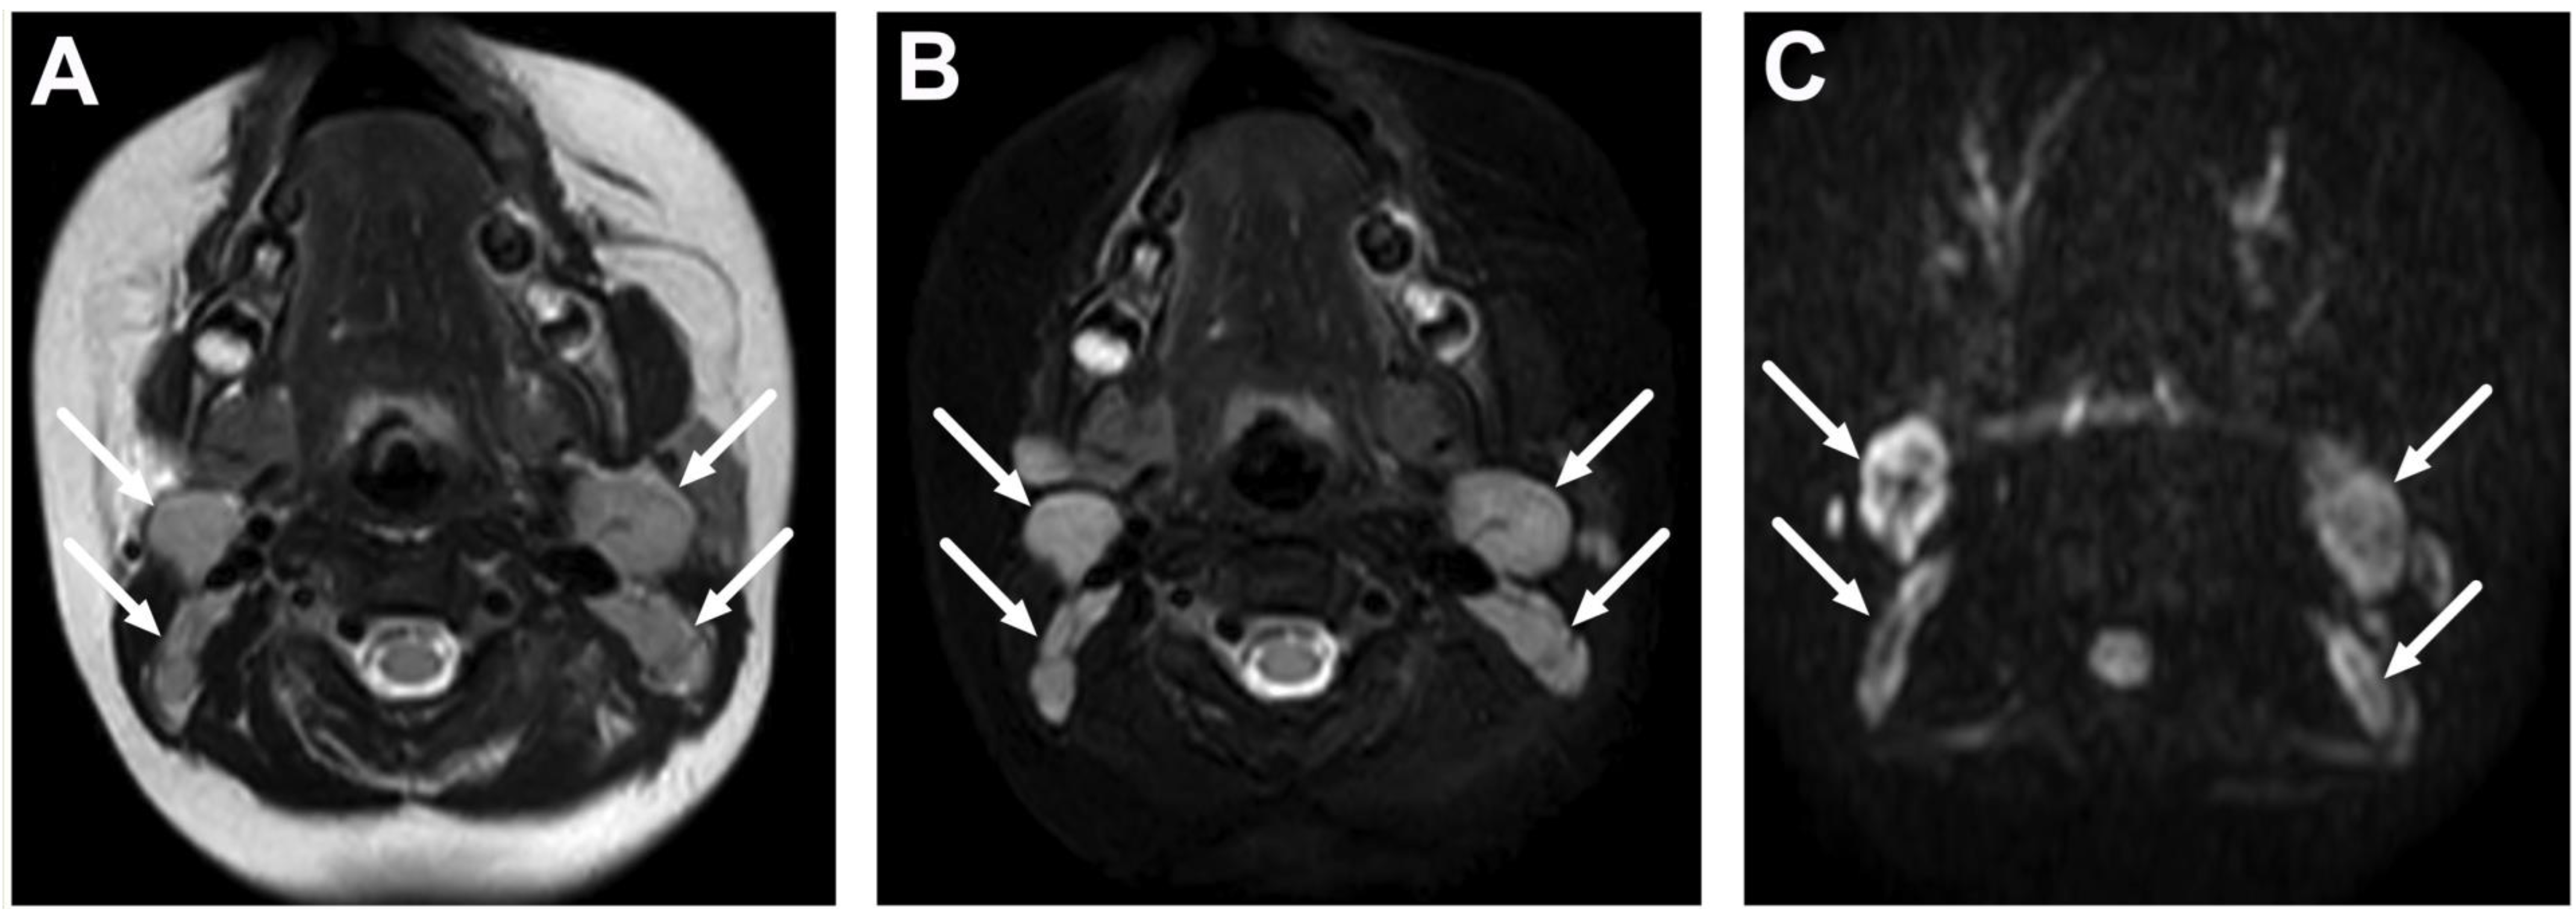

| Abscess | T1 SE T2 Dixon (water) DWI post-contrast T1 Dixon (water) | Non-enhancing collection with low ADC values enclosed in abnormally enhancing soft tissue edema. | Detection of an abscess usually requires operative consideration and exact abscess location, and extensions are useful in operative planning. | Abscesses may have an intermediate T2 signal content; blood products and/or postoperative status may complicate abscess assessment; necrotic lymph nodes may be misinterpreted as suppurative lymphadenitis. |